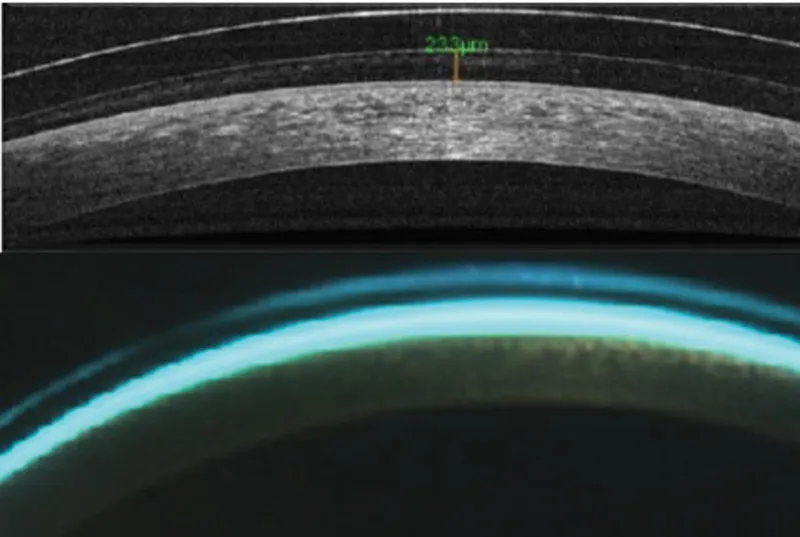

Anterior Segment OCT

⭐ Clinical Pearl: Anterior segment OCT reveals subclinical corneal changes 2-3 weeks before slit lamp detection. Epithelial thinning >10 micrometers centrally indicates chronic mechanical stress, while stromal thickening >20 micrometers suggests hypoxic edema requiring immediate intervention